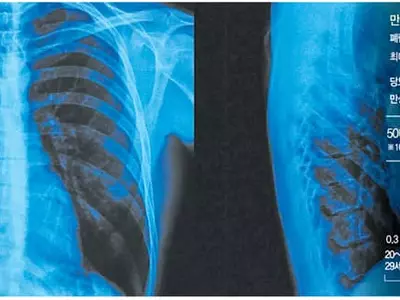

폐암보다 무서운 폐렴… 노인엔 치명적

고열·기침·가래 1주 이상 지속기운·식욕 없고 자꾸 졸리다면적정평가 1등급 병원 찾아가야노인·만성질환자·면역저하자폐렴구균 ..